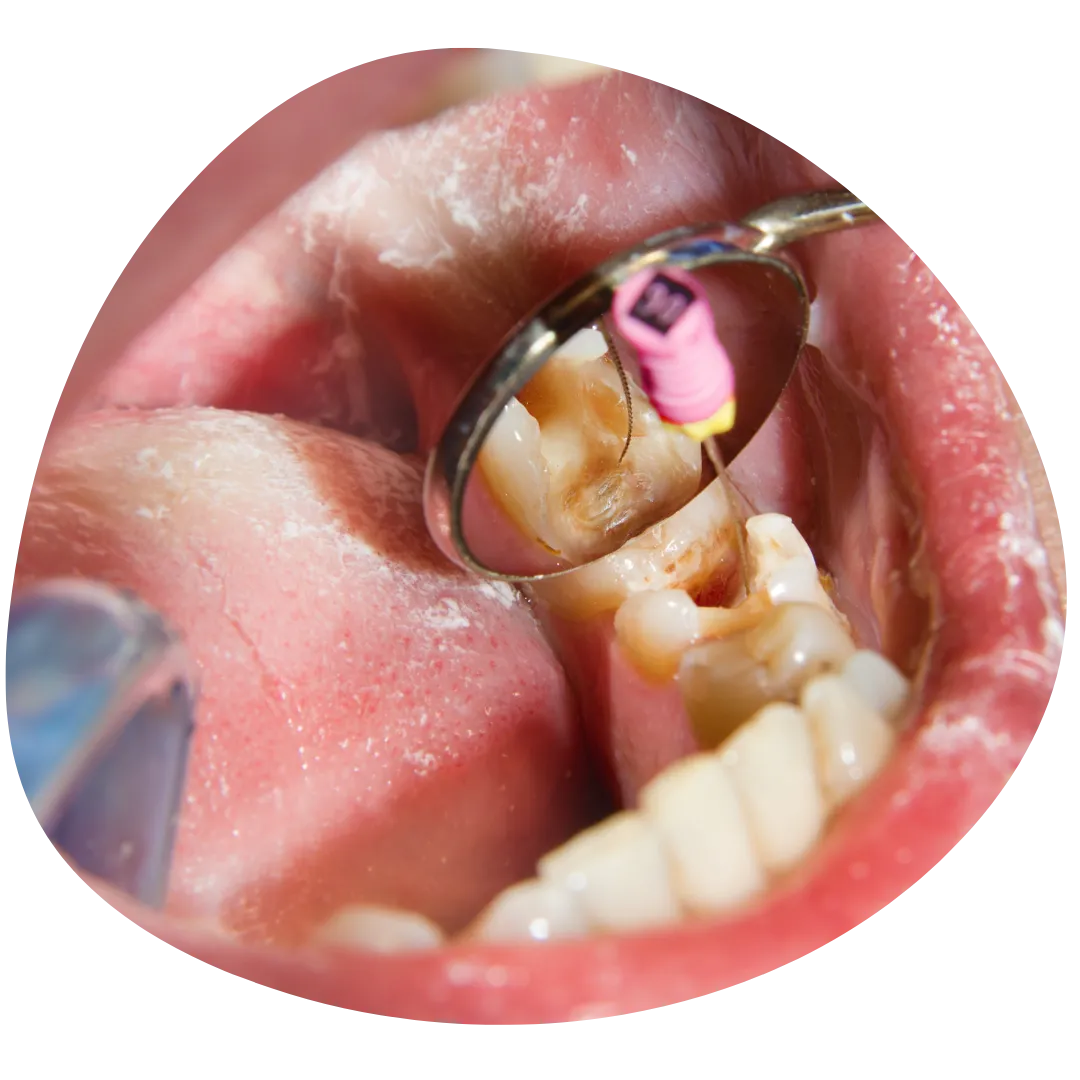

Endodoncija, poznata i kao liječenje kanala korijena, ključna je za spašavanje zuba koji je ozbiljno oštećen ili zaražen. U Dental Studio dr. Jusić, pažljivo uklanjamo inficirano tkivo iz unutrašnjosti zuba, čistimo kanale i ispunjavamo ih biokompatibilnim materijalom. Ovaj postupak ne samo da eliminira bol i infekciju, već i sprječava potrebu za vađenjem zuba, omogućavajući Vam da zadržite prirodan osmijeh i funkcionalnost zuba.

Endodontska terapija u Dental Studio dr. Jusić pruža brojne prednosti, uključujući očuvanje Vaših prirodnih zuba i prevenciju daljnjih dentalnih problema. Dr. Jusić koristi najnoviju tehnologiju i moderne metode kako bi osigurali precizno i bezbolno liječenje. Pored toga, individualni pristup svakom pacijentu omogućava nam da prilagodimo terapiju vašim specifičnim potrebama, što rezultira bržim oporavkom i dugotrajnim rezultatima.